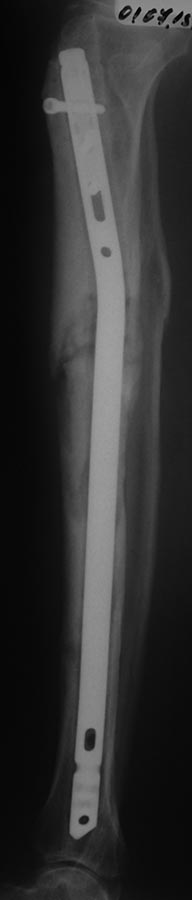

еще снимок. Эти снимки 01.07.2015 г.